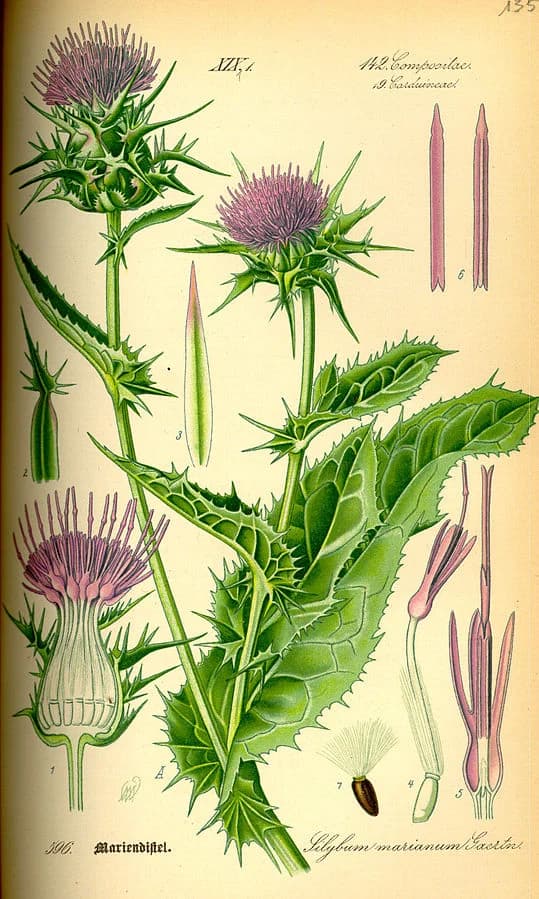

The 18+ Benefits of Milk Thistle (Silybum marianum) and Mechanisms

Milk Thistle: More than Just a Liver Support

Milk thistle has been used for over 2000 years as a remedy for ailments of the liver, kidney and gallbladder. R

Milk thistle is an annual or biennial plant of the Asteraceae family, native of souther Europe through to Asia. R

Germany is the largest producer of milk thistle using it for dyspeptic complaints and various amounts of liver conditions. R R

Milk thistle works primarily by silymarin, an active flavonoid, by protecting the liver as an antioxidant and as an anti-inflammatory.

In publications, milk thistle is labeled as: R

- Carduus marianus

- Legalon

- Mariendistel

- Milk thistle

- Silybin

- Silybum marianum

- Silybum

- Silychristin

- Silydianin

- Silymarin